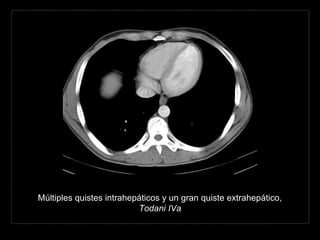

Múltiples quistes intrahepáticos y un gran quiste extrahepático,

Todani IVa